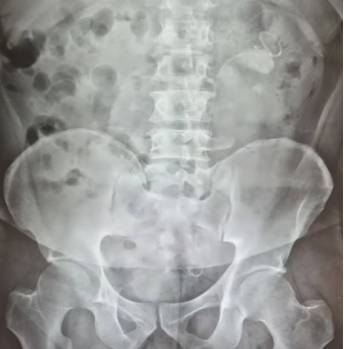

(术后影像学检查显示结石已全部取出)

两周后,医生再次手术将患者左肾内多颗结石一一击碎并吸出。至此,形成“石街”的源头问题得到解决,肾功能也逐渐恢复。